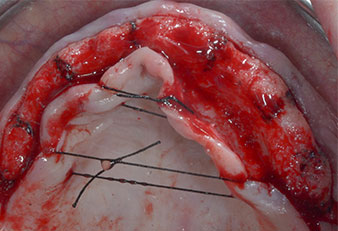

Tres años después, llegó el momento de colocar una prótesis del mismo tipo en el maxilar superior. Basándose en una planificación mediante tomografía computarizada de haz cónico (CBCT, por sus siglas en inglés), se evitó la necesidad de realizar una elevación del seno utilizando implantes cortos, mientras que una plantilla quirúrgica sirvió para transferir las posiciones planificadas al borde alveolar (figuras 1 y 2).

Para marcar las posiciones del implante y realizar la preparación piloto, se utilizó un inserto piezoeléctrico (Piezomed I1) con revestimiento de diamante y forma de llama (figura 3). Se tomaron precauciones para realizar movimientos hacia arriba y hacia abajo, con una potencia reducida, una irrigación completa y una baja presión (por debajo de 300 g). A continuación, se aplicó un inserto piloto (Piezomed I2A/I2P) para aumentar el diámetro inicial de 2 mm de los sitios de implante (figura 4), seguido de un inserto de 3 mm (Fig. 5).

En el caso que nos ocupa, no se utilizaron los insertos Z25P ni Z35P debido a la existencia de un hueso posterior relativamente blando, que se trató sin problemas con el I3A/I3P.

Debido al hueso relativamente duro (D2) existente en el sector anterior, los sitios de los implantes largos de 10 mm de las posiciones 11 y 21 se finalizaron con una fresa rotatoria de 4 mm de diámetro, en combinación con un contra-ángulo quirúrgico WS-75 L de W&H, el motor de implantes Implantmed de W&H y el módulo opcional Osstell ISQ de W&H. En cambio, debido a la existencia de hueso blando, los sitios posteriores se prepararon hasta un diámetro final de 3 mm utilizando el inserto Piezomed I3P. Por último, los implantes se colocaron a nivel crestal para su osteointegración durante tres meses (figuras 6-10). La prótesis existente se mantuvo sobre cuatro implantes provisionales (figura 8).